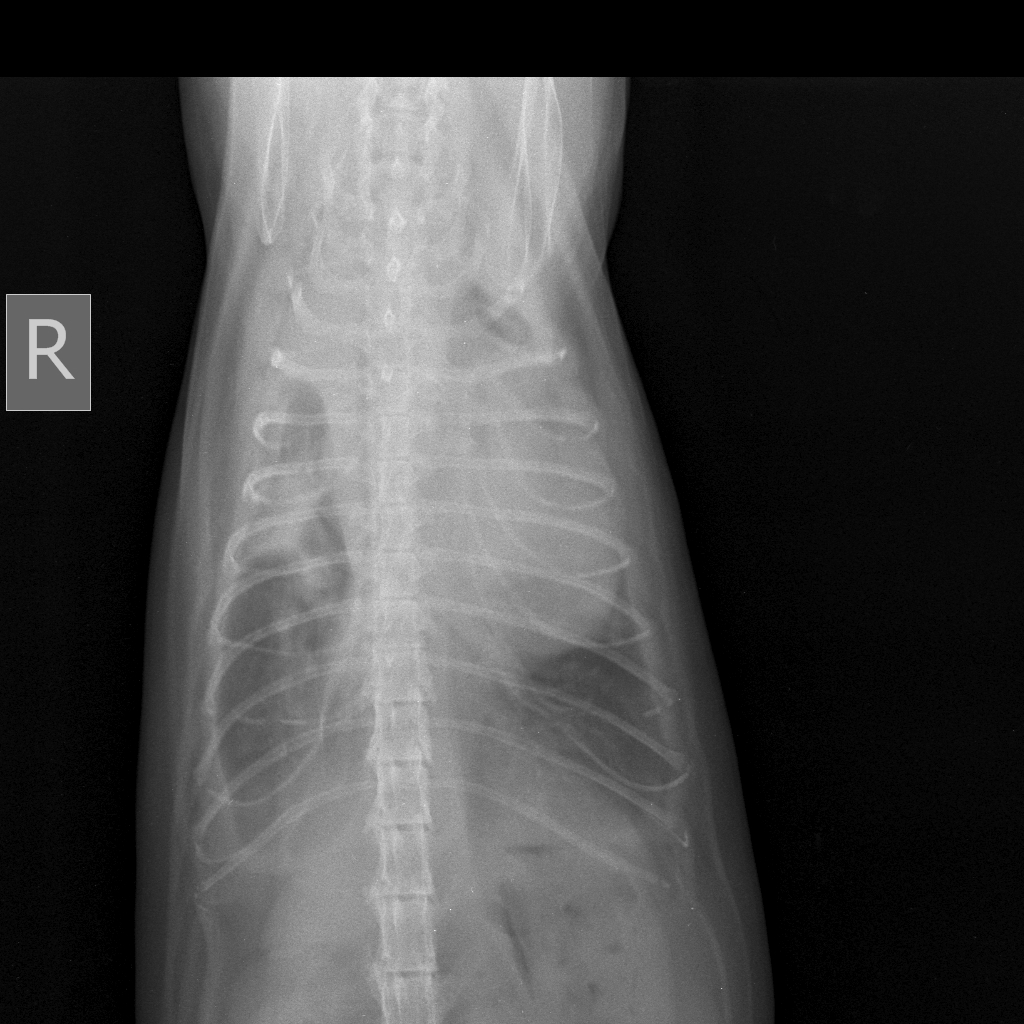

Здравствуйте!Помогите пожалуйста!! У нашей кошки 2 года проблемы со здоровьем.Частое дыхание ( с частотой 50-55 в мин),мокрый кашель и хрипы.Врачи думают что жидкость,откачивали эту жидкость 2 раза.Хотя говорят,что жидкости совсем мало,но всё равно делают пункции.Назначают мочегонные препараты.Но ей не становится лучше |

[21.07.2019 16:14] Здравствуйте! Судя по снимкам у кошки увеличено сердце.Рекомендую сделать УЗИ сердца и получить консультцию у кардиолога. |

[21.07.2019 18:03] Есть зона просветления в краниальной части. Но необходимо смотреть сам снимок(его можно увеличить), а не картинку. |

[21.07.2019 22:30] В легких воздух должен быть(более темный фон должен быть),а там наоборот. Может быть жидкость,а может быть просто фото такое. Поэтому необходимо смотреть непосредственно снимок. |